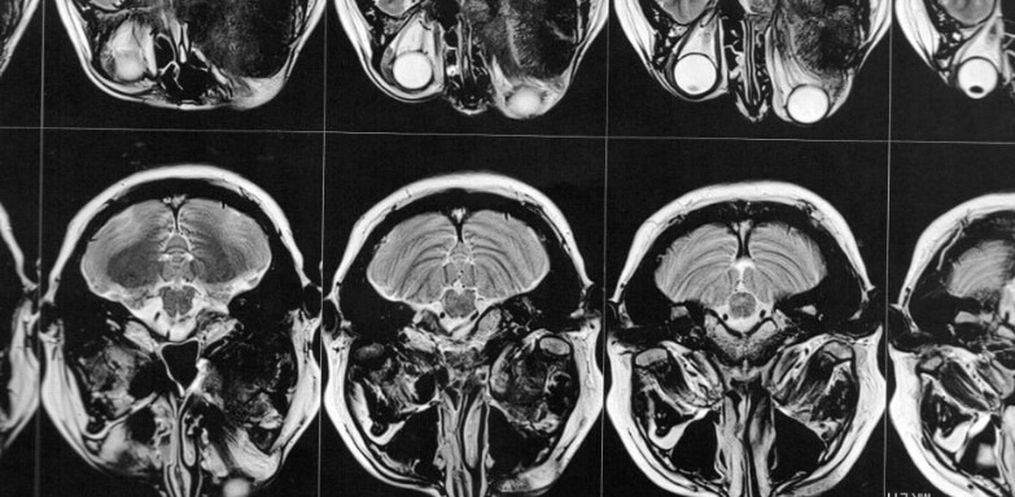

Então este médico solicitou exames de imagem (ressonância magnética e tomografia) para avaliar a situação, os quais foi constatado que o meningioma ainda está ali, e que continua empurrando o olho e se expandindo para outras áreas. Trata-se de um meningioma gigante (medindo 6 x 6,6 x 6 cm), que está localizado na placa do assoalho da fossa média e anterior.

A cirurgia deverá ser feita de urgência, pois o meningioma continua se expandindo, e pode comprimir o olho esquerdo afetando a visão que lhe resta. Também pode comprimir outras partes do cérebro, ou pior ainda, causar a morte.

O médico também disse que será necessário realizar dois procedimentos cirúrgicos, um para retirada do tumor, e o segundo para realocar o olho para seu lugar e implantar a prótese onde o osso foi retirado.